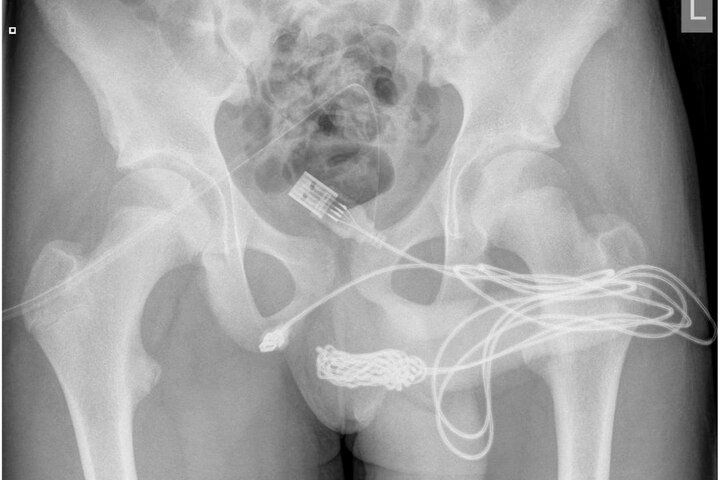

Das Röntgenbild zeigt den Verlauf des USB-Kabels in der Harnröhre des Teenagers.

Teenager misst seinen Penis mit dem USB-Kabel: Spital!